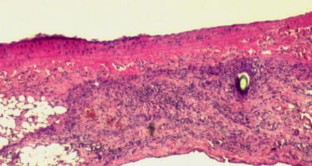

Former animal studies on laser-assisted microvascular anastomosis performed with CO2-, argon-, diode-, Holmium:YAG- and Nd:YAG-lasers had already proven the stability of the anastomotic sites. Tissue damage remained minimal along the anastomosis, while duration of the surgeries decreased significantly compared to that of traditionally implemented microvascular sutures. In addition to this, foreign body reaction next to end-to-end anastomosis appeared to be minimal due to fewer traditional stitches. This animal study was designed in order to investigate the durability and the histological properties of microvascular anastomosis assisted by KTP-532 laser. Twenty-one Wistar albino rats were used: in nine animals the KTP-laser-assisted microvascular anastomosis was carried out on the femoral artery. Those nine animals were divided into three groups and each of them consisted of three rats. The animals in these three groups were sacrificed 4 h, 1 and 4 weeks following the surgery, respectively. In three additional animals laser-assisted microvascular anastomosis was done on the abdominal aorta. Conventional microvascular sutures were carried out on femoral arteries of further nine animals in the control group. The healing process of the femoral arteries is documented with figures of histological slides both in the laser-treated and in the conventionally operated group of rats. The KTP-laser-assisted microvascular anastomosis failed on the abdominal aorta, as strong bleedings occurred after the traditional sutures had been taken out. However, the coagulative effect of the KTP-laser could still be used. The authors share the opinion that the success of the laser-assisted end-to-end microvascular anastomosis does not depend on the wavelength of the applied laser, but can be affected by both the calibre of the vessel and the intraluminal pressure.

Fig. 1

Fig. 2

Fig. 3

Fig. 4

Fig. 5

Fig. 6

Fig. 7

Fig. 8

Fig. 9